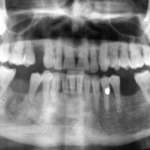

Il workflow digitale nel carico immediato Premium

Viene documentato un case report, progettato e finalizzato attraverso un workflow digitale, per la realizzazione di una protesi superiore a supporto implantare e a carico immediato entro le 48 ore successive alla chirurgia